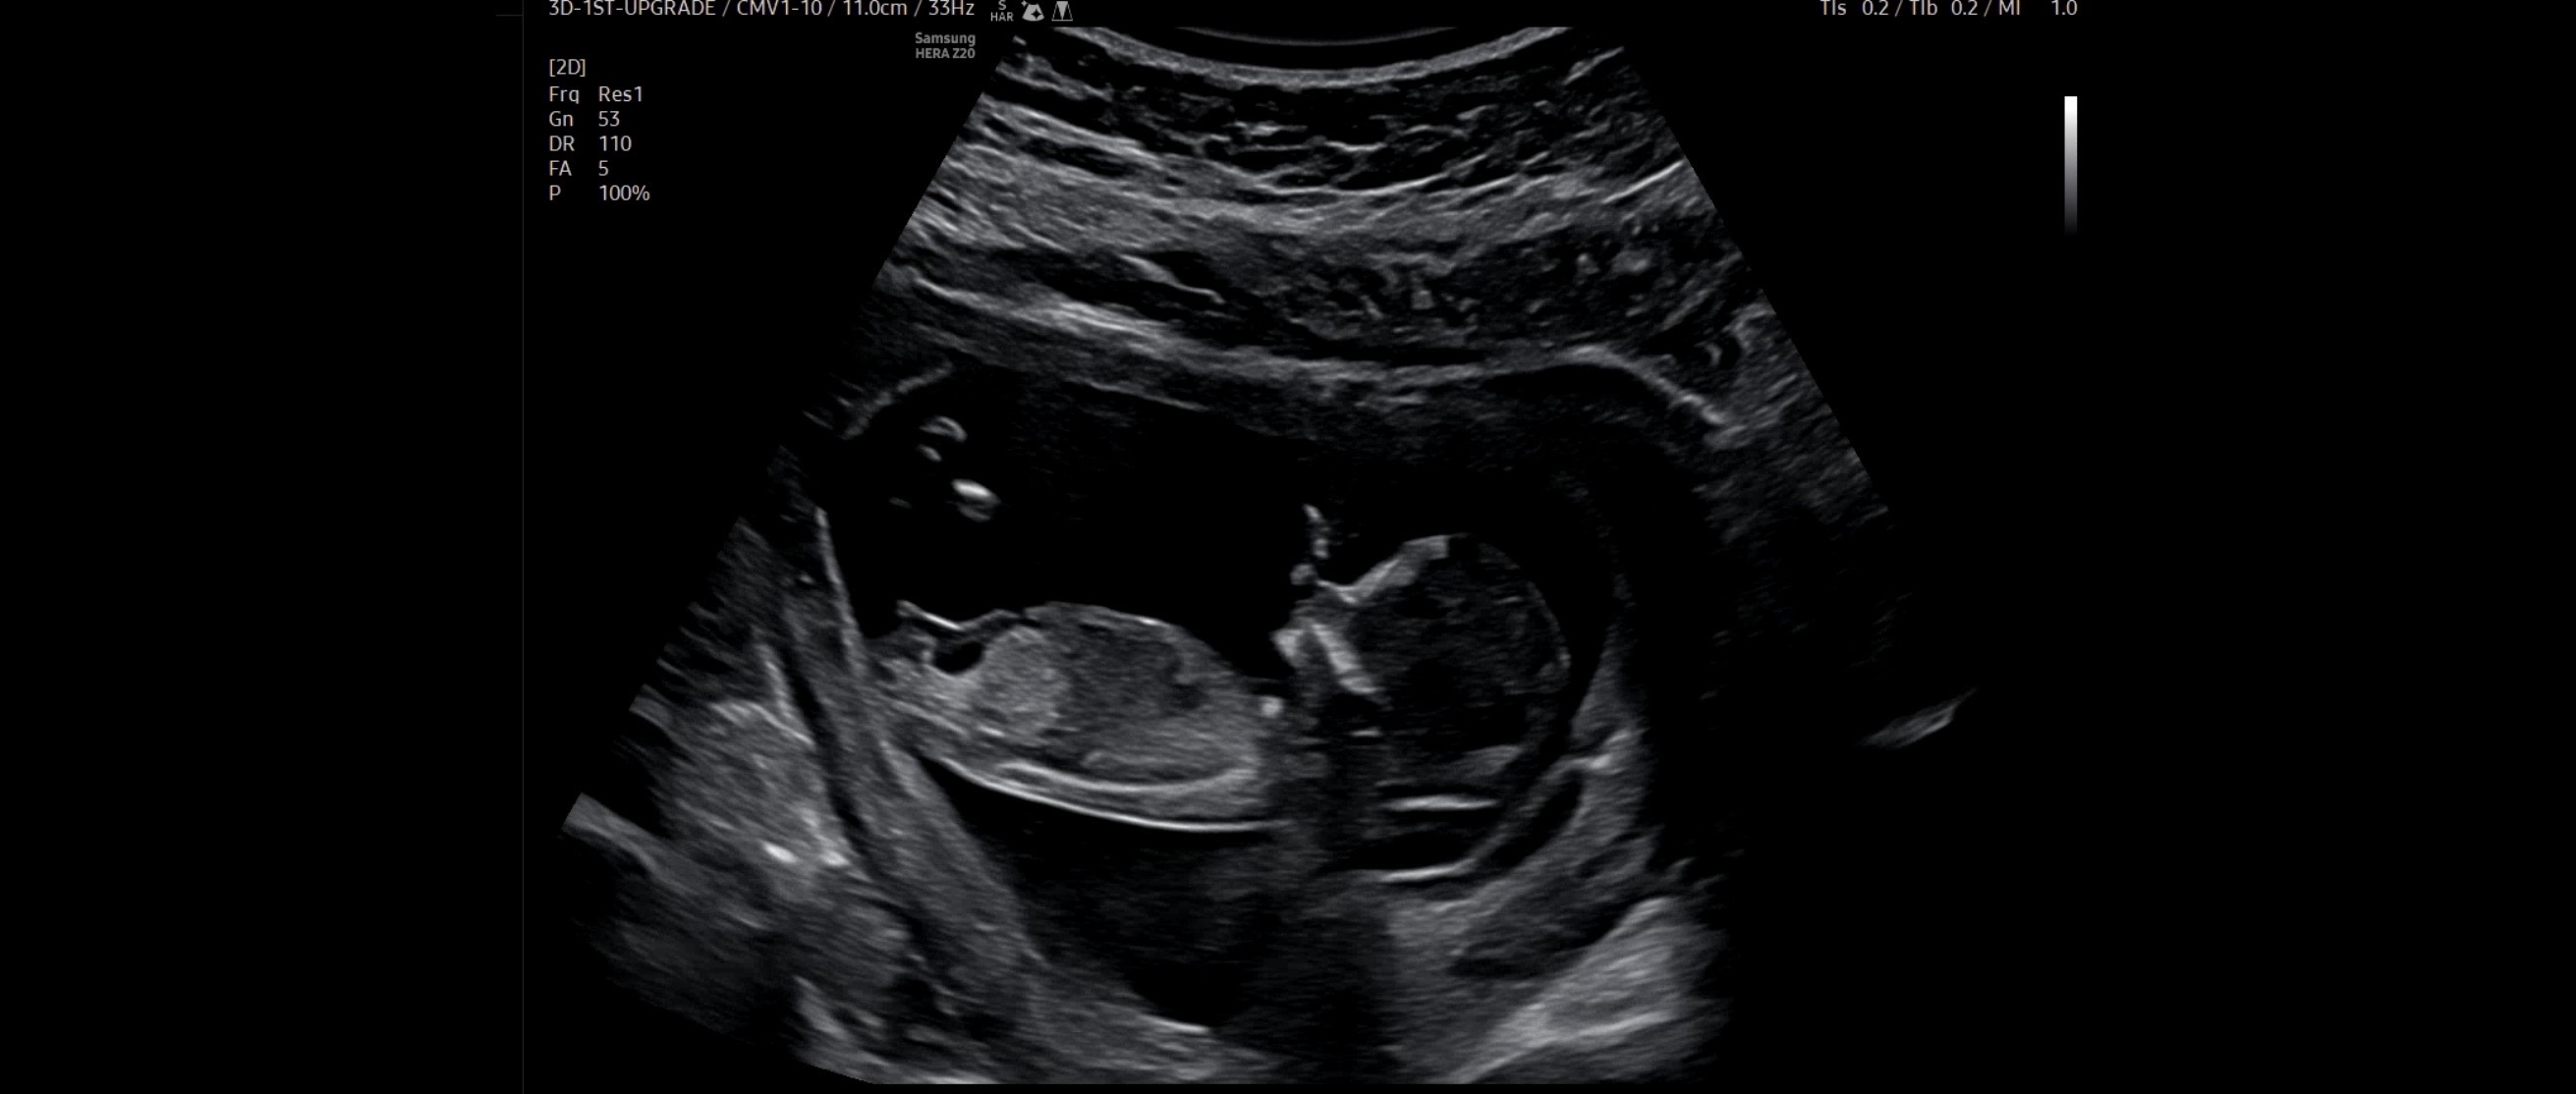

12주3일차 각도법 추측 부탁드려용🙏🏻

의견이 너무나 반반이라🥹 봐쥬시면 감사하겠습니다